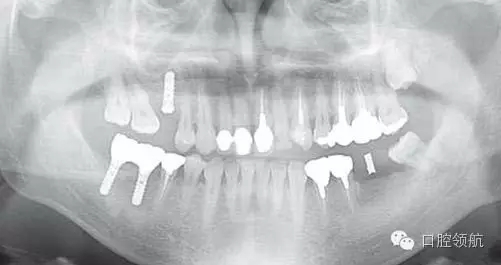

患者,38歲,男性,作為需要全面治療的患者來院?;局委熀螅蚁骂M磨牙區(qū)及右上頜磨牙區(qū),還有拔牙后的左下頜磨牙缺損區(qū),擬進行種植修復(fù)。圖1為初診時的曲面斷層影像,問診,模型診斷,曲面斷層檢查均未見異常,因此,最先在右下頜磨牙缺損區(qū),繼而在右上頜磨牙缺損區(qū)植入種植體,這些種植體愈合良好。

圖1 初診時的曲面斷層影像。